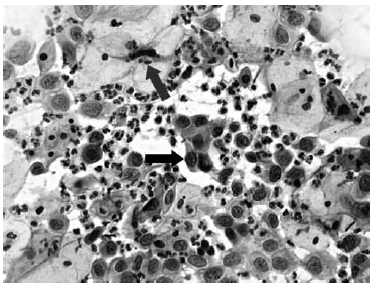

Nas questões de números 46 a 60, assinale a alternativa que melhor corresponde ao diagnóstico do quadro microscópico apresentado.